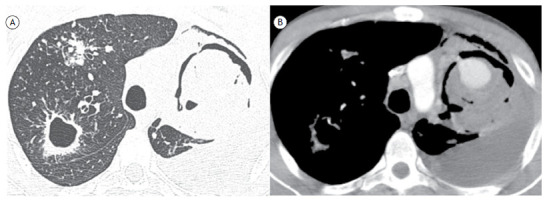

Rasmussen's aneurysm.